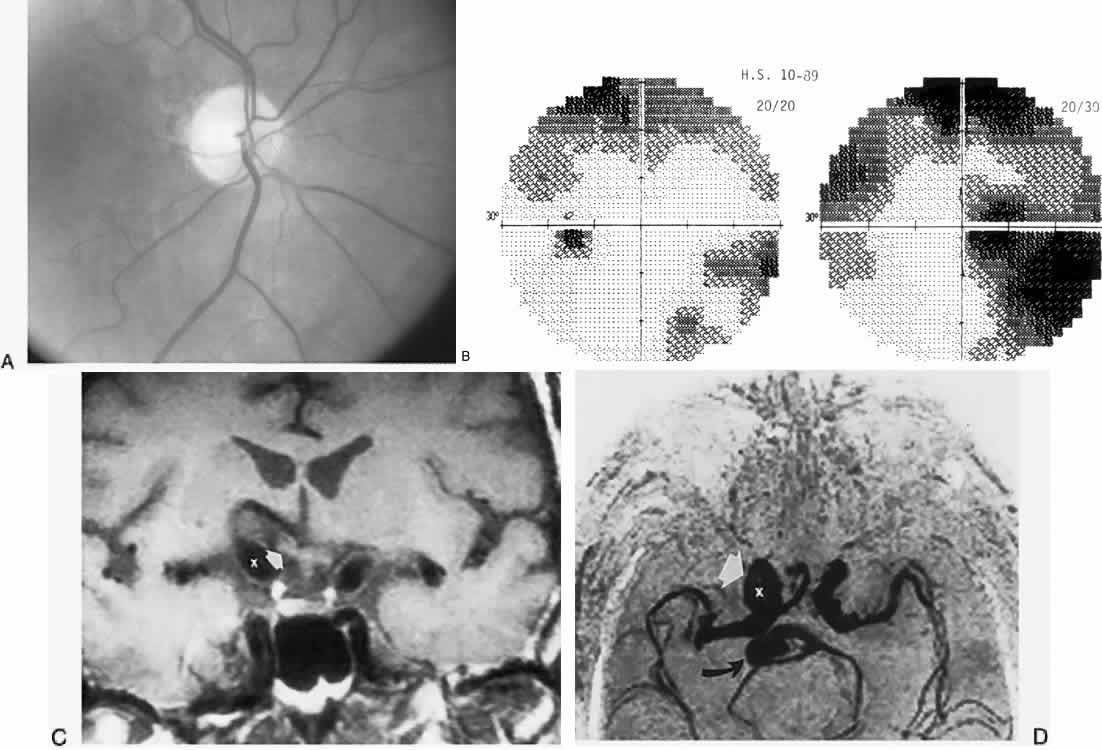

The retinal variety may be admixed in a person who suffers the more conventional attacks of migraine. It is presumed that vasospasm in the retinal circulation determines transient hypoxia, perhaps somewhat similar to the visual cortical event. On rare occasions, the fundus has been examined during typical retinal migraine episodes, and arterial constriction has been described. Wolter and Burchfield106 photographically documented such an episode and demonstrated mild “retinal edema”; vessel narrowing is also evident (Fig. 8). Fortunately, permanent complications of retinal migraine are rare. These may take the form of central retinal artery occlusion or ischemic papillopathy (see Volume 2, Chapter 16); nerve fiber bundle visual field defects may be demonstrated (Fig. 9).

Fig. 8. Retinal migraine. A. During amaurotic episode. Note the dusky appearance of the fundus, increased retinal sheen (possibly edema), and dark narrowed veins (arrows). The disc is also hyperemic. B. Fundus after episode. Compare paired arrows. (Courtesy of Dr. J. Reimer Wolter)

Fig. 9. An 18-year-old student with recurrent episodes of left retinal migraine. After a typical attack, he noted an inferior field defect. A. Fundus shows a defect in the superior arcuate nerve fiber bundle (between arrows: compare fiber layer below disc). B. Visual field defect corresponds to a retinal nerve fiber layer defect.